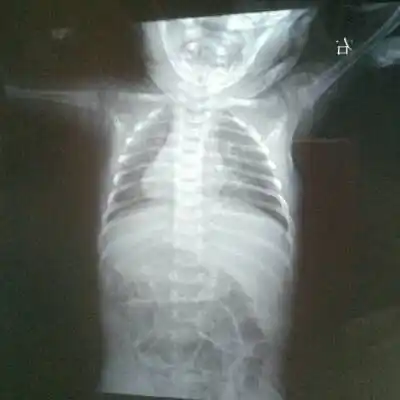

新生儿30天得肺炎,现在在妇幼icu,这是胸片,很严重吗

这几组患儿胸片是肺炎还是正常影像规培医师懵了